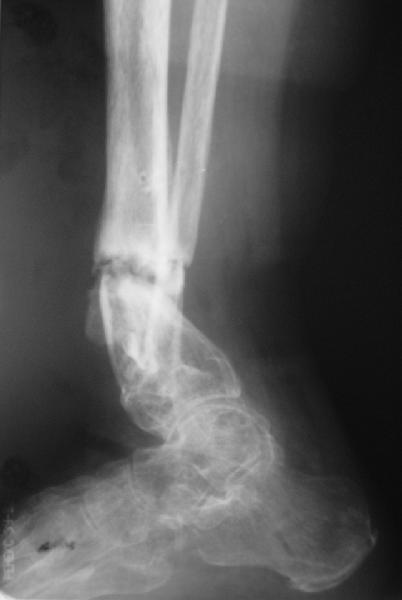

Alexander Chelnokov 26 Апрель 2005, 11:11

e> Какова была подвижность в зоне несращения после остеотомии малоберцовой

e> кости?

Примерно такова, как было на снимках в аппарате. Все, что относительно свободно было, выбрали, а дальше уже было тугое сопротивление тканей.

e> Была ли возможность одномоментной коррекции оси б.б кости и если да,

e> то почему не штифтование, а аппарат?

Аппарат - чтобы плавно исправить ось. В приложении - снимки на момент окончания коррекции в аппарате, фото с операции, и послеоперационная рентгенограмма.

Диаметр гвоздика 10,5 мм. Пришлось укорачивать до 23 см - уж очень миниатюрная дама, отверстия насверлил под 45 градусов, под 5 мм винты. По оси удалось сблизить до этого положения. Заперли гвоздь пока статически с планом через 2 месяца верхний винт убрать. Но это ей придется уже в Ташкенте сделать. Что скажете? Спасибо.

In attachment - x-rays at the end of alignment, the surgery, and result. The nail was cut to 23 cm. Four 45 degree holes were pre-drilled at the distal nail tip. The nail was locked statically

after some impaction. Dynamization is considered in 8 weeks. Any comments/critics?

Отправитель: Nuno Craveiro Lopes 27 Апрель 2005, 02:10

Alex,

> In attachment - x-rays at the end of alignment, the surgery, and

> result. The nail was cut to 23 cm. Four 45 degree holes were

> pre-drilled at the distal nail tip. The nail was locked statically

> after some impaction.

Amazing! How can you find the pathway of the nail through all those wires and the distal screws through so much hardware?